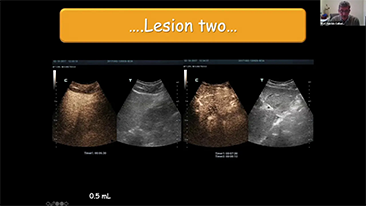

Comment voir le foie au mieux??

L'imagerie de contraste joue un r?le important en cas de lĂŠsions hĂŠpatiques focales, par exemple hĂŠmangiome ou cancer hĂŠpatique. La technologie d'imagerie de contraste UWN+ ultra-large et non linĂŠaire offre une meilleure pĂŠnĂŠtration, un rapport contraste-tissu plus ĂŠlevĂŠ, avec un index mĂŠcanique (IM) plus faible et une observation plus longue du temps de perfusion.